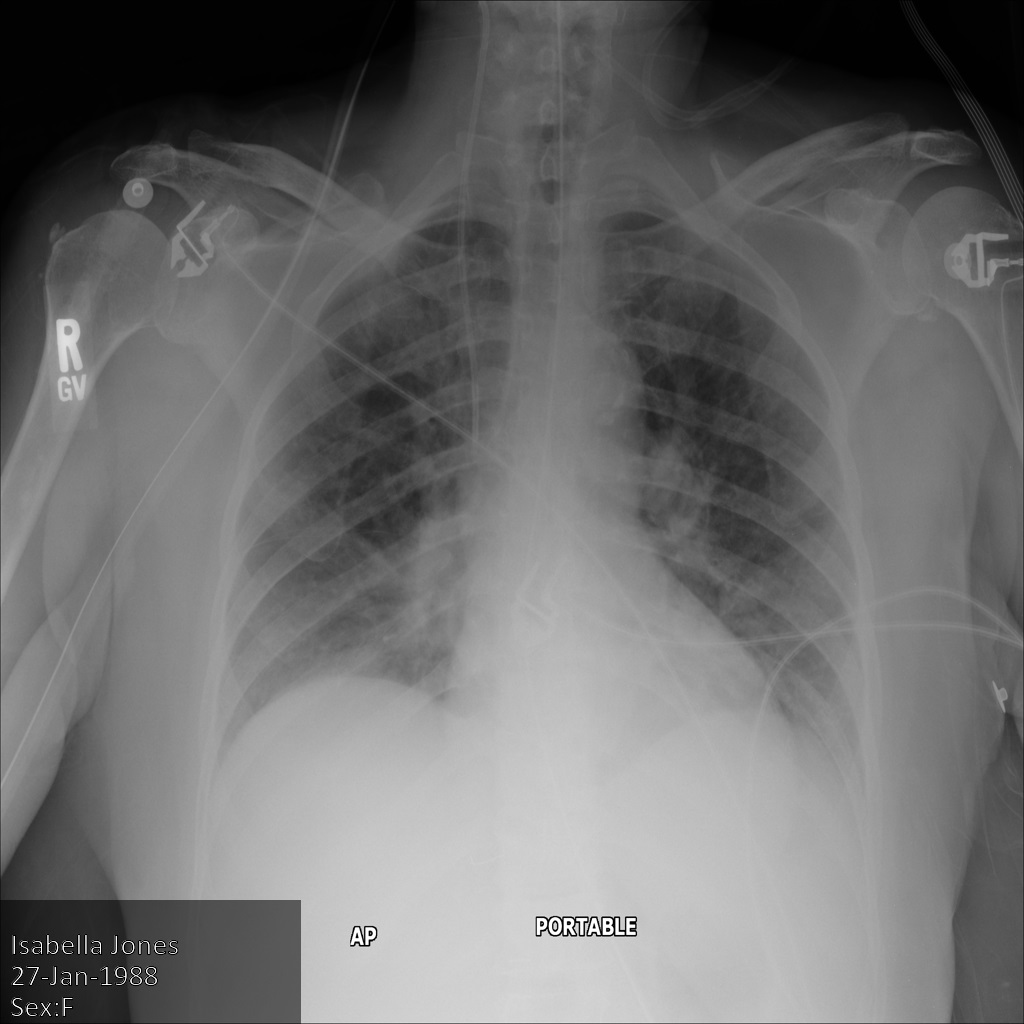

En la siguiente imagen, se muestra una radiografía sin ocultamiento de un paciente:

Después de enviar la imagen a la API de Cloud Healthcare mediante la opción REDACT_SENSITIVE_TEXT, la imagen aparece de la siguiente manera:

Puedes ver que ocurrió lo siguiente:

- Se ocultó el elemento

PERSON_NAMEen la esquina inferior izquierda de la imagen - Se ocultó el elemento

DATEen la esquina inferior izquierda de la imagen

El sexo del paciente no se ocultó porque no se considera texto sensible de acuerdo con los Infotipos de DICOM predeterminados.